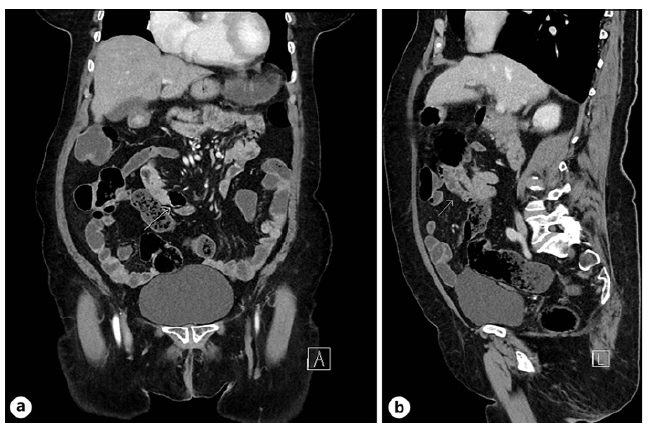

Abdominal computed tomography revealed hernia-tion of intestinal loops through the fossa of Waldeyer associated with partial mesenteric torsion without up-stream dilation, compatible with a right paraduodenal internal hernia. Within these herniated jejunal loops, several small bowel diverticula were noted, the largest measuring 28 mm (shown in Fig. 2a, b).

Fig. 2 a Right paraduodenal internal hernia identified in abdominal computed tomography (arrow indicates diverticulum) - coronal plane. b Right paraduodenal internal hernia identified in abdominal computed tomography (arrow indicates herniated intestinal loop) - sagittal plane.